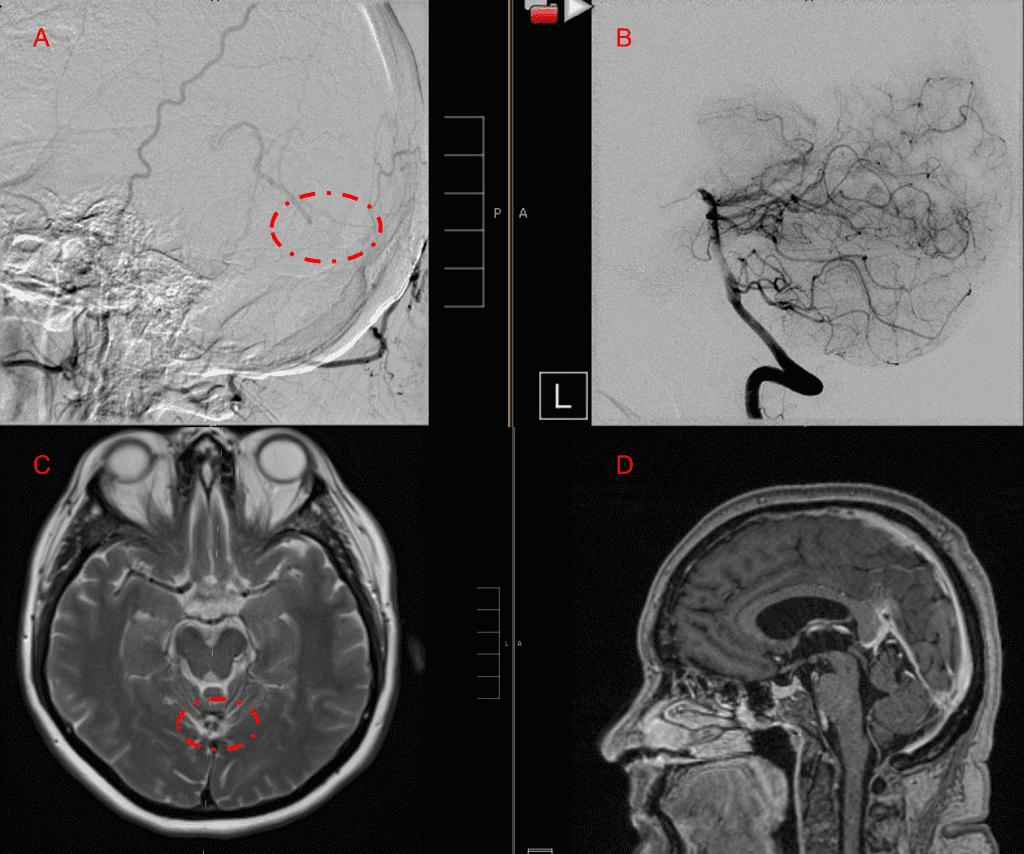

Figure 5. Bilateral ECA Lateral angiograms (A and B) demonstrates small residual indirect supply To the AVM from the bilateral Occipital arteries.

Embolization was successful at immediately reducing the pressure into the Aneurysmal Varix with greater than 90% reduction in A-V shunts. After an intensive period of critical care monitoring and care for her initial brain hemorrhage, she made a near complete recovery with mild intermittent left sided paresthesias and generalized deconditioning. After receiving inpatient and outpatient Acute Rehabilitation, Physical, and Occupational therapy, she completely recovered all of her Activities of Daily Living (ADLs) at 3 months and achieved an modified Rankin Scale (mRS) of 0. On follow-up angiography, small residual low flow A-V shunts were identified and targeted for Gamma Knife Radiosurgery (Figure 5 and 6).